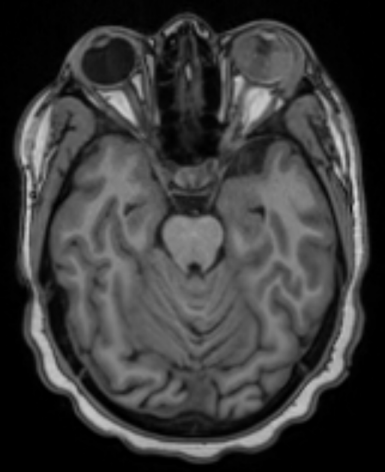

We present the case of a 15-year old girl with a history of B-cell acute lymphoblastic leukemia (t(1:19)) in clinical remission for two years. She was under maintenance chemotherapy with dexamethasone, mercaptopurine, and melphalan. In the past year, she was also suffering from pulmonary tuberculosis having completed 9 months of therapy. She presented in our ophthalmology emergency room with acute visual loss of the left eye (LE) and ocular redness for 5 days. Best corrected visual acuity in her RE was 20/20 and absence of light perception in her left eye (LE). Intraocular pressure upon presentation was 12 mmHg in RE and 22 mmHg in LE. In LE biomicroscopy, she presented with a very small hypopyon, small, inferior, keratic precipitates, anterior chamber cells 4+, vitreous cells 3+, and a dense white mass was visible in the vitreous cavity along with organized vitreous hemorrhage (Figure 1 [Fig. 1]). The fundoscopy examination was made difficult by the dense vitritis. It was possible to perceive the presence of a white vitreous mass occupying most of the vitreous cavity and vitreous hemorrhage. Biomicroscopy and fundoscopy were normal in LE. B-scan ultrasound showed a multilobulated vitreous mass occupying practically the entire ocular globe with associated superior choroidal detachment (Figure 2 [Fig. 2]). An orbital and cranial MRI revealed an intraocular mass with gadolinium enhancement and lacrimal gland enlargement (Figure 3 [Fig. 3]).

Figure 3: Orbital and cranial MRI revealed an intraocular mass with gadolinium enhancement and lacrimal gland enlargement. No signs of CNS metastasis were found.